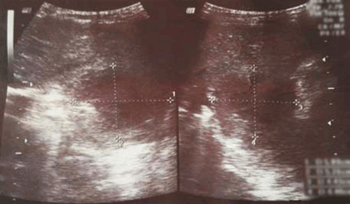

En la evolución persistió febril, con dolor abdominal difuso, manteniendo buen estado general. Por la persistencia de la sintomatología se reiteró la radiografía de tórax, que no evidenció cambios con respecto al estudio anterior. Se realizó una ecografía tóraco-abdominal que mostró una tumoración en el lóbulo izquierdo del hígado de 58 mm de diámetro mayor y 44 mm de diámetro menor (Figura 2). Tras ese hallazgo se realizaron tomografía computada (TC) y resonancia magnética (RM) de abdomen que evidenciaron una tumoración hepática única, en lóbulo izquierdo, sin elementos que permitieran identificar claramente su origen.

Figura 2: Ecografía abdominal: tumoración en el lóbulo izquierdo del hígado.